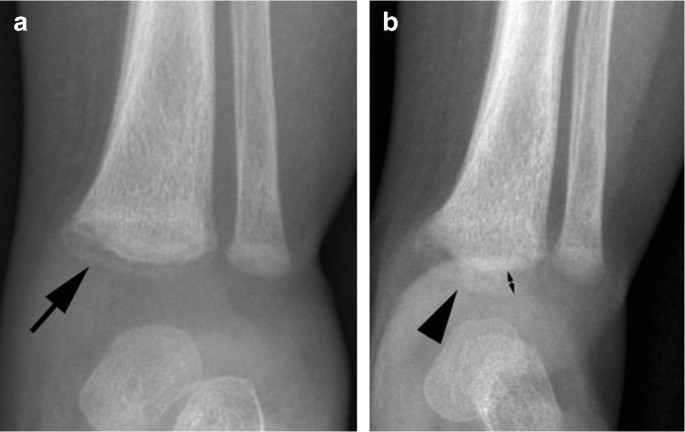

These metaphyseal abnormalities were identified from postmortem radiogra-phy and correlated with microscopy . The au-thors concluded the metaphyseal alterations represented partial or complete planar micro- fractures that transected the primary spongio-sa adjacent to the growth plate . These micro- fractures usually resembled a "bucket-handle"

Specific fractures . A number of fractures have been recognised as highly specific to non-accidental injuries (rather than accidental injury) . They include: metaphyseal fracture (so-called bucket handle fracture or corner fracture ) present in up to 39-50% of abused infants <18 months; said to be virtually pathognomonic of NAI; rib fractures

radiological dating of fractures and even less relating fractureagetochildabuse . Themostcomprehensivereview is byO'ConnorandCohen .' . . . Fresh fractures , including metaphyseal fractures , have sharply defined margins . With the development of an osteoclastic response to necrotic bone the fracture ends